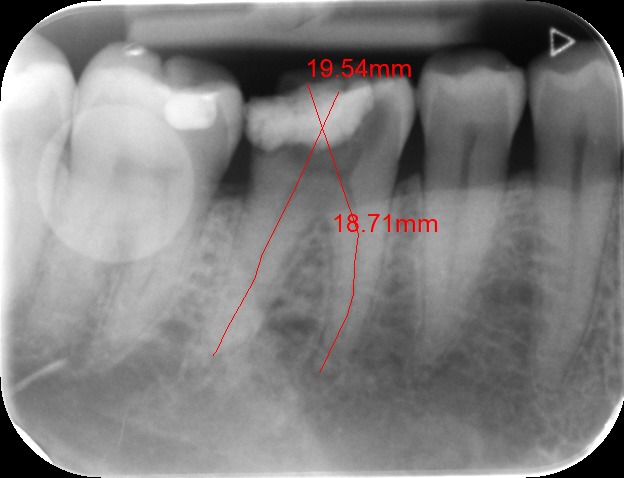

During the consultation, the dentist will first listen to your concerns and carry out appropriate tests to identify the right tooth that is causing pain. As a part of the diagnosis, your dentist will carry out various clinical tests to identify the right tooth and will take some radiographs which can aid in the diagnosis.

An access cavity is placed on the surface where the patient bites, to reach the root canals of the tooth. Once all the canals are identified, small files are used to remove the infected pulp.

Files of different sizes are used to eliminate bacteria and infection and to shape the canals. The canals are disinfected thoroughly with irrigants and later the canals will be sealed in 3 dimensions with a special medicament called gutta-percha to prevent reinfection of the tooth and the access cavity will be sealed with a temporary filling.